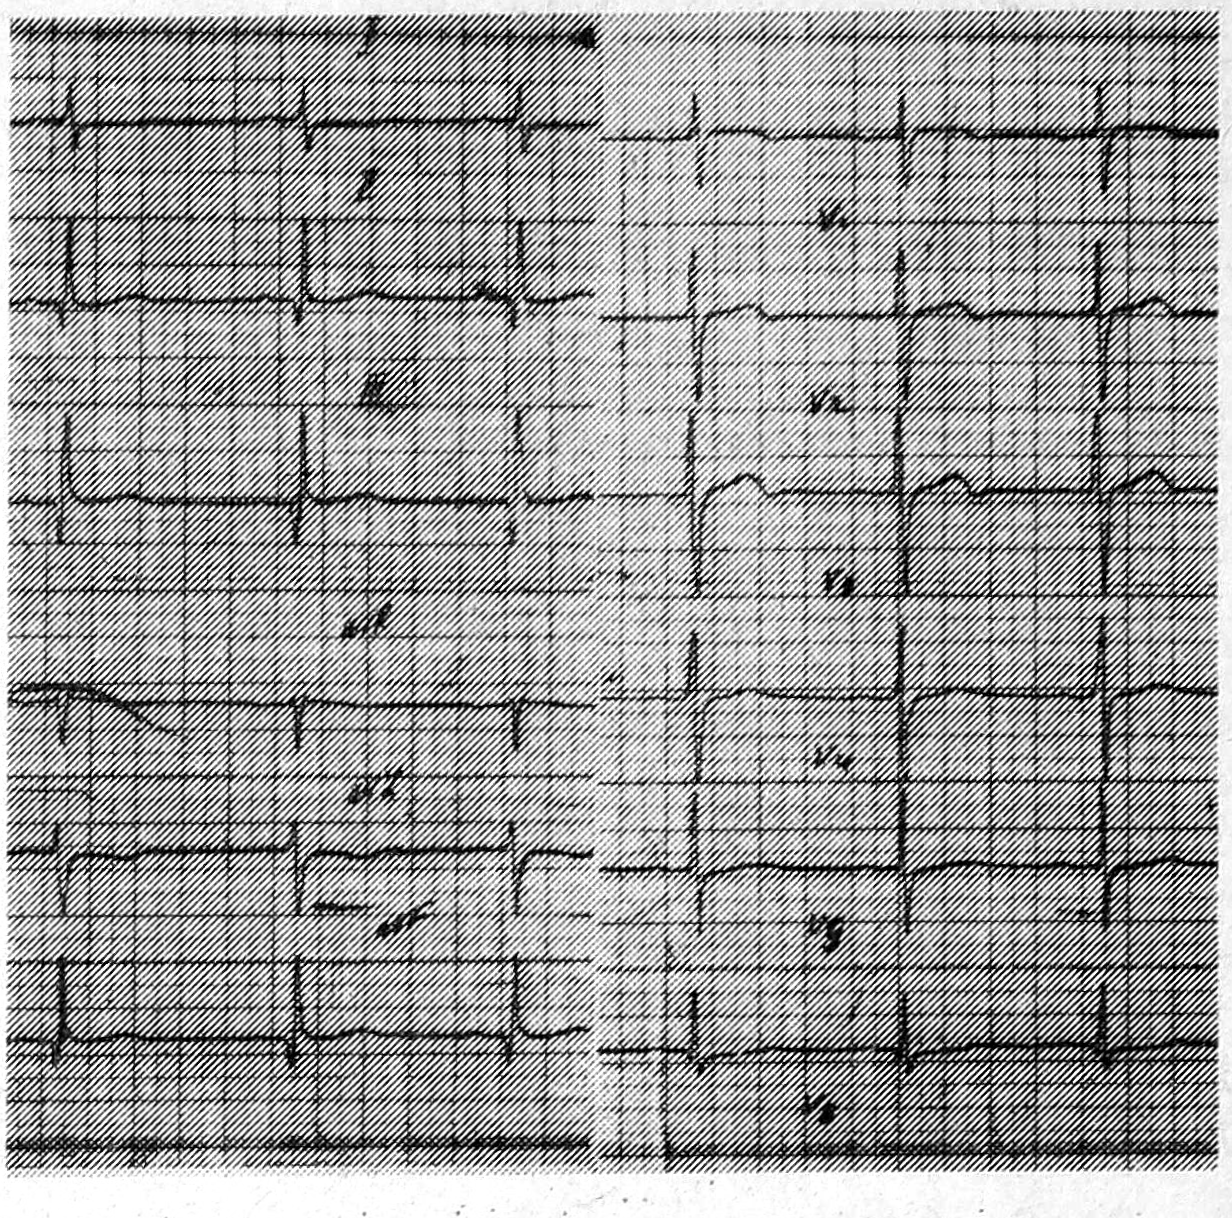

На ЭКГ (рис. 1); ритм синусовый, вертикальное положение электрической оси сердца, в отведениях II, III, avF зубцы Q глубиной 5—9 мм и шириной до 0,04 с, высокие зубцы R в отведениях V1—V3.

Рис. 1. ЭКГ больного Н., 27 лет.